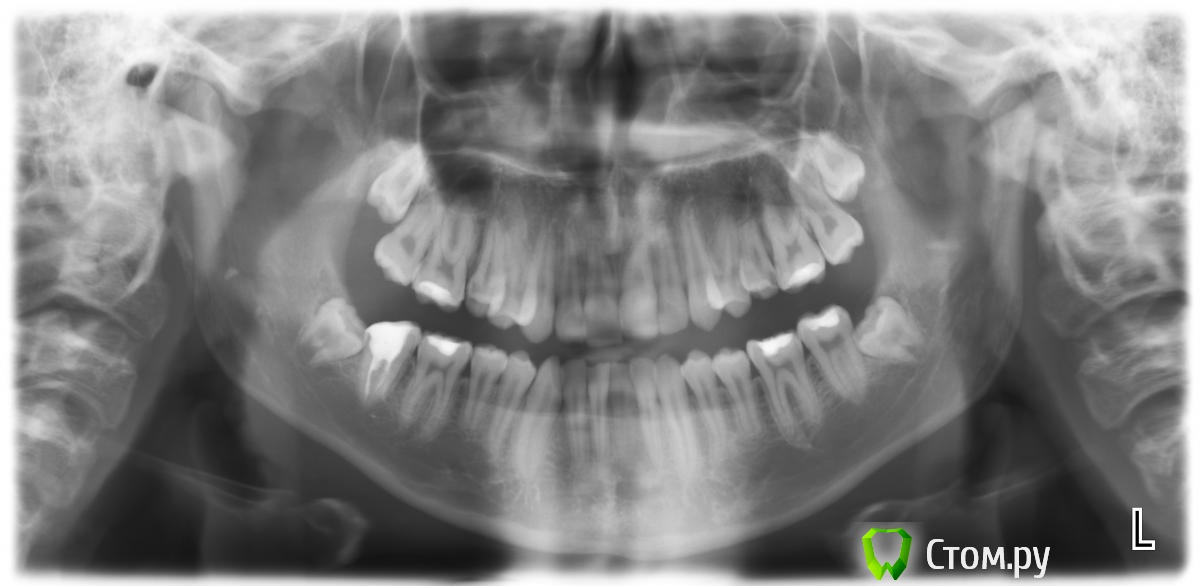

Jamex Опубликовано 30 мая, 2014 Поделиться Опубликовано 30 мая, 2014 Здравствуйте!Я начинающий ортодонт, помощи и совета особо спрашивать не у кого, поэтому не обессудьте и,пожалуйста, подскажите решение проблемы.Интересует,как можно выровнять окклюзионную плоскость на верхней челюсти, в книге прочел, что это делается избирательным подвязыванием интрузионной дуги,но как практически это осуществить не очень понимаю. И про среднюю линию вопрос, как ее выровнять в конкретном случае и каков вообще принцип выравнивания средней линии. Ссылка на комментарий

m.d.n Опубликовано 30 мая, 2014 Поделиться Опубликовано 30 мая, 2014 Дайте больше информации. модели оптг трг фото полноценные.Случай который вы взяли сложный- не для начинающего доктора. Ссылка на комментарий

Jamex Опубликовано 30 мая, 2014 Автор Поделиться Опубликовано 30 мая, 2014 Дайте больше информации. модели оптг трг фото полноценные.Случай который вы взяли сложный- не для начинающего доктора.да,для меня пока сложновато, поэтому прошу у вас помощи и совета.Здесь фотографии до лечения,сейчас ситуация как на фото в первом посте. Нужно плоскость выровнять окклюзионную. Ссылка на комментарий

m.d.n Опубликовано 30 мая, 2014 Поделиться Опубликовано 30 мая, 2014 да,для меня пока сложновато, поэтому прошу у вас помощи и совета.Здесь фотографии до лечения,сейчас ситуация как на фото в первом посте. Нужно плоскость выровнять окклюзионную.а а почему трг с разомкнутыми челюстями?.тут 3 класс закомуфлированный Ссылка на комментарий

m.d.n Опубликовано 31 мая, 2014 Поделиться Опубликовано 31 мая, 2014 (изменено) Вы можете помочь мне с лечением данного пациента?снимите с верхней челюсти дугу на пару недель. сделайте фото оклюзальное фронт и боковые - мне ненравиться как спозиционированы брекеты .удалить 8 нижние . Изменено 31 мая, 2014 пользователем m.d.n Ссылка на комментарий

Ayrat_zub Опубликовано 10 июня, 2014 Поделиться Опубликовано 10 июня, 2014 (изменено) если по теме, ортоимплатном тянете сейчас?с нижней челюстью как решили вопрос? по видимому протрузия резцов имеется.. протсо приклеили брекеты, дополнительно ничего не делали?фото нынешние еще нужно бы глянуть) Изменено 10 июня, 2014 пользователем Ayrat_zub Ссылка на комментарий

Викторовна575 Опубликовано 12 июня, 2014 Поделиться Опубликовано 12 июня, 2014 За одно и верхние 8-е надо удалить,расположение их явно не самое удачное,побольше фотографий нынешней ситуации Ссылка на комментарий